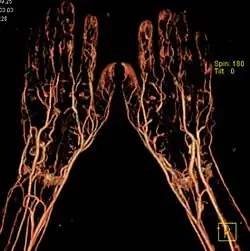

Многослойная компьютерная томография со внутривенным контрастным усилением и трёхмерной реконструкцией изображения

Многослойная («мультиспиральная», «мультисрезовая» компьютерная томография — МСКТ) была впервые представлена компанией Elscint Co. в 1992 году. Принципиальное отличие МСКТ от спиральных томографов предыдущих поколений в том, что по окружности гентри расположены не один, а два и более ряда детекторов. Для того, чтобы рентгеновское излучение могло одновременно приниматься детекторами, расположенными на разных рядах, была разработана новая — объёмная геометрическая форма пучка.

КТ-ангиография позволяет получить послойную серию изображений кровеносных сосудов; на основе полученных данных посредством компьютерной постобработки с 3D-реконструкцией строится трёхмерная модель кровеносной системы.